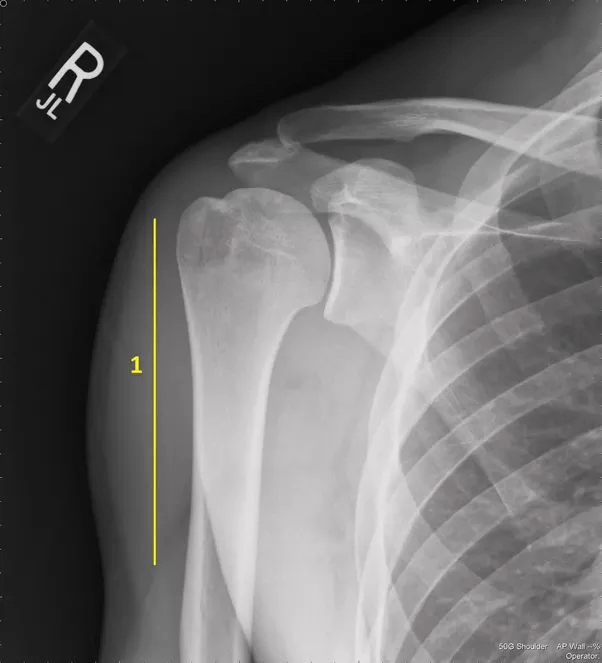

Trẻ em có nhiều xương hơn so với người lớn: Cơ thể người trưởng thành có 206 xương, nhưng ở trẻ sơ sinh con số này khoảng 300. Cùng nhìn vào một chiếc xương cánh tay của em bé dưới đây:

Bạn có nhìn thấy 2 khúc xương được đánh dấu màu vàng không? Chúng là hai phần của cùng một chiếc xương. Giữa hai khúc này là một thành phần mềm và đàn hồi giống cao su, được gọi là đĩa sụn (được đánh dấu bằng mũi tên màu xanh).

Phần sụn này chính là nơi xương phát triển khi một em bé dần dần trưởng thành. Khi trẻ dần đến tuổi dậy thì, đĩa sụn này bắt đầu quá trình vôi hóa (biến thành xương) và hợp hai mảnh xương thành một mảnh duy nhất – đây chính là lí do tại sao chúng ta thường ngừng cao sau tuổi dậy thì.

Quan sát những tấm hình này, chúng ta cũng biết rằng khi xương phát triển, nó phát triển nhiều hơn ở hai đầu nơi có đĩa sụn thay vì ở giữa.Đây là hình ảnh xương cánh tay của một người lớn sau khi đĩa sụn đã thành xương: